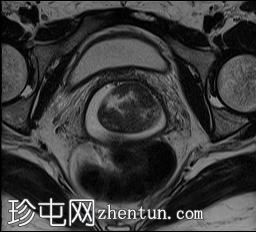

轴位

T2加权像

可见局部晚期浸润性内生型宫颈癌,肿瘤大小为30 x 32 x 48 mm。该肿瘤已侵犯宫颈前唇和后唇的深层间质,以及子宫肌层的下段。

此外,肿瘤还累及宫旁组织。影像学检查发现异常淋巴结肿大,最大短轴直径(SAD)为10 mm,位于髂总血管分叉处和髂内动脉链下方。该淋巴结肿大在弥散加权成像(DWI)上显示水限制,且增强扫描后可见强化。

宫内节育器(IUD)位于子宫内正常位置。左侧子宫底壁内肌瘤大小为15 x 16 mm(FIGO 4期)。子宫内膜厚度约为3 mm,未见宫腔内病变。双侧卵巢外观正常,未见实性或囊性病变。